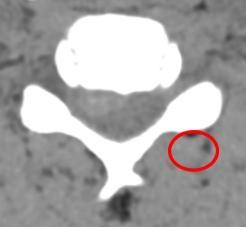

何飞平主任医师团队详细问诊查体,安排相关检查,影像学检查提示:颈C5/C6椎间盘脱出,压迫神经根。与患者及家属沟通病情后,决定予以行手术治疗。

▲颈椎CT、MRI提示:颈C5/C6椎间盘脱出。